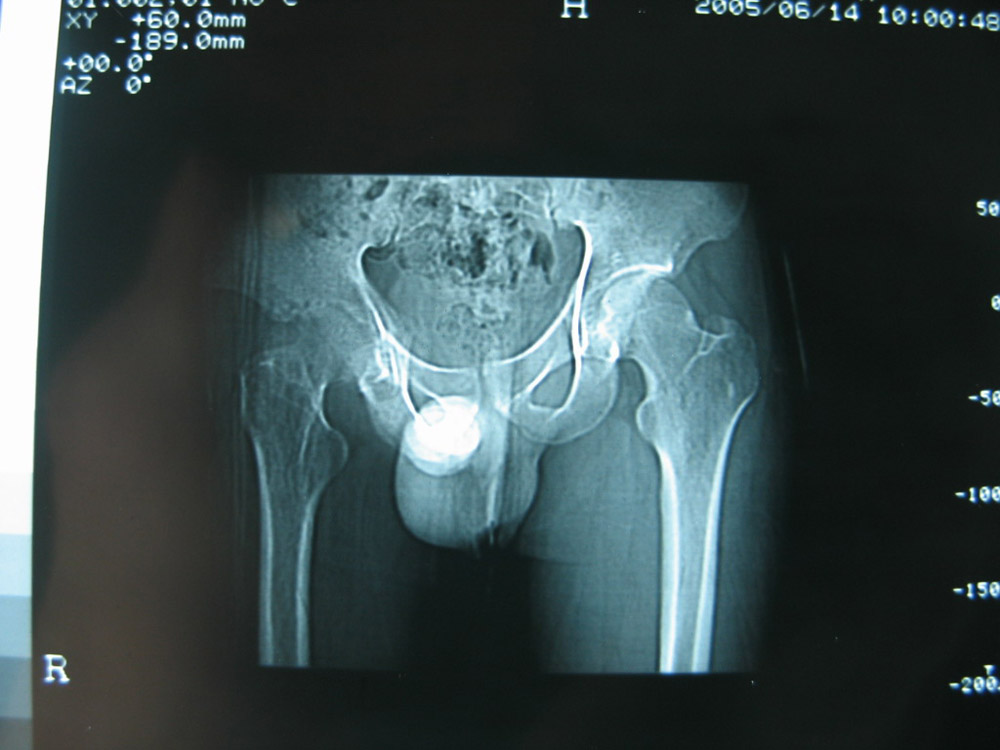

以下是引用卜一在2007-1-25 16:33:00的发言:[br]右侧髋关节股骨头及髋臼骨骨小梁疏松 粗糟,股骨头外形毛糟,软组织似肿胀,间隙略变窄.考虑:1 髋关节结核可能性大.2 缺血性坏死?3 化脓性髋关节炎?

以下是引用hhcckk在2007-1-25 17:18:00的发言:[br][br]支持髋关节结核,[br]依据关节面破坏,有脓肿,脓腔内有钙化,关节周围增生不明显,鉴别[br]1化脓性的病变增生明显,临床上有高热[br]2创伤引起的关节炎,无菌坏死不会引起关节面的破坏,而且不会在这么短的时间内出现[br]